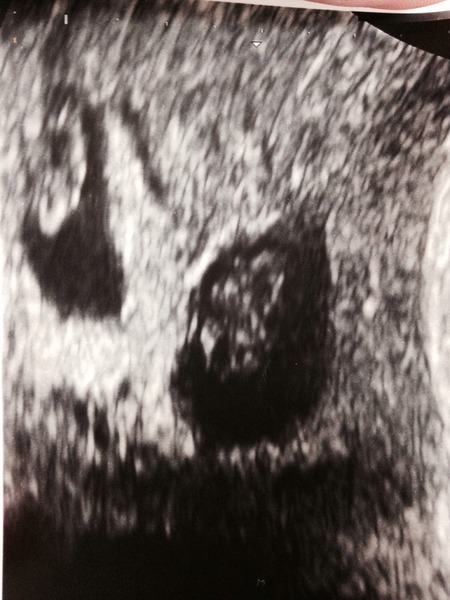

CocklesandMussels · 01/04/2016 17:11

We have had our scan, and it's twins! I'm in shock and DH looked like he was going to pass out. A photo of two tiny blobs with heartbeats is enclosed.

Have a good weekend everyone x